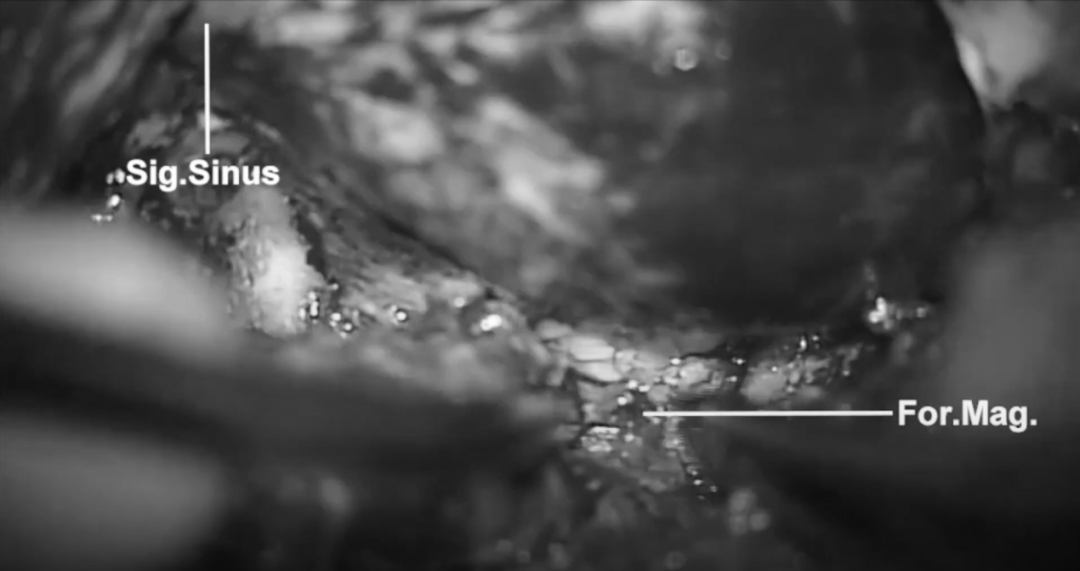

乙狀竇后髁上入路開骨瓣后,暴露乙狀竇及枕骨大孔,磨除枕骨大孔外側(cè)緣,包括髁狀窩,使橄欖核周圍的小腦延髓池廣泛暴露。硬腦膜沿乙狀竇切開,切口向下延伸穿過大孔。

從小腦延髓池釋放腦脊液后,小心翼翼得解剖顱神經(jīng)、脈絡(luò)叢、PICA和椎動脈,仔細觀察了延髓的外側(cè)部分,注意保護后組顱神經(jīng)、PICA及通向髓質(zhì)的穿支等。

“橄欖核“腦干安全區(qū)及病變的定位

術(shù)中可以看到由正常腦干實質(zhì)覆蓋的病變,及其引起的含鐵血黃素改變和輕微的表面隆起,使用90°剝離指小心細致的分離病變,在舌下神經(jīng)起點后方穿刺,經(jīng)軟腦膜切開橄欖區(qū)。病變不是外生的,而是位于切口的正下方。

延髓的手術(shù)安全操作區(qū)。A,延髓橫斷面示有 3 個手術(shù)安全操作區(qū):前外側(cè)溝,橄欖區(qū)及延髓后外側(cè)溝;B,延髓前外側(cè)觀,示進入橄欖區(qū)和前外側(cè)溝的區(qū)域,緊位于舌下神經(jīng)根下方;C,后面觀示后正中溝和后外側(cè)溝手術(shù)安全操作區(qū)。